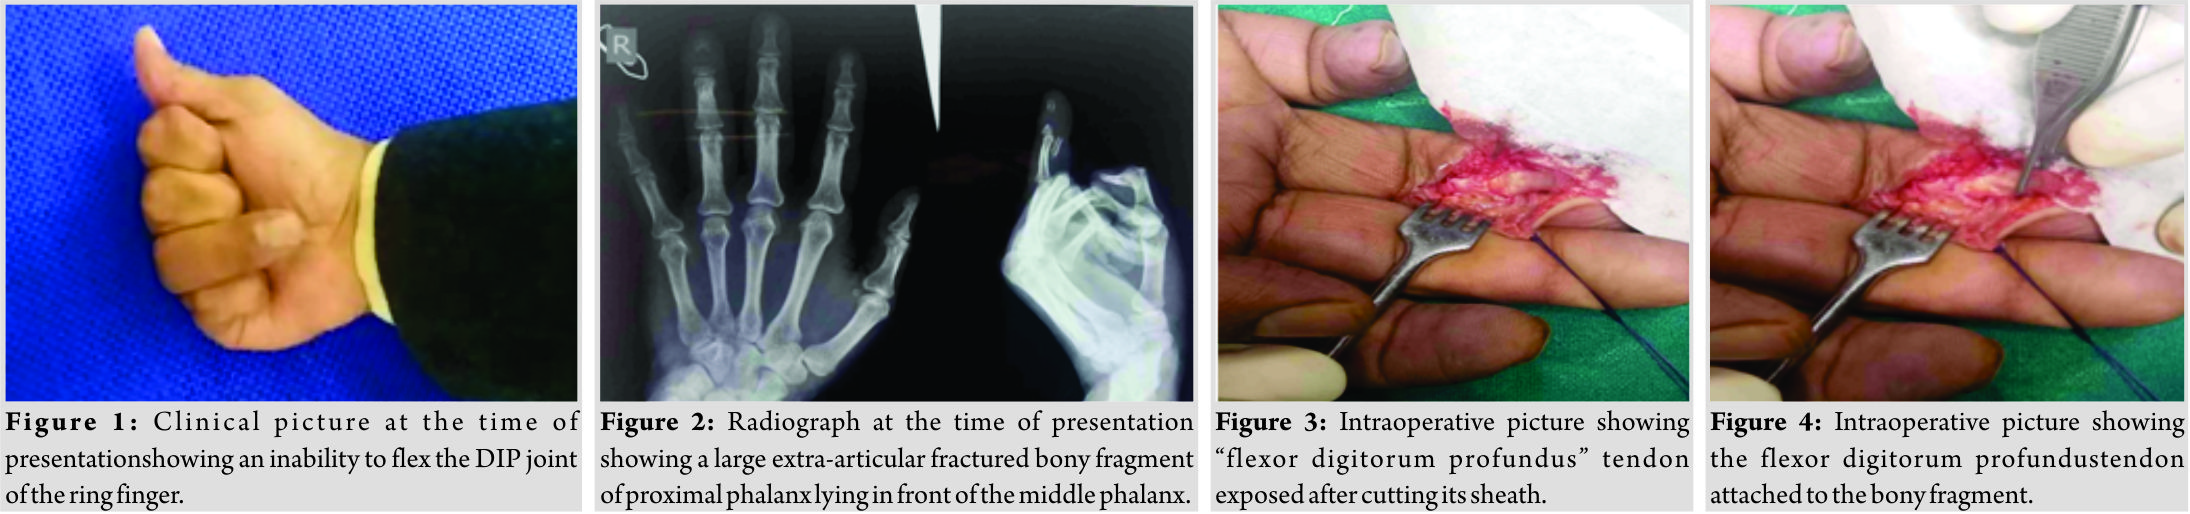

A 45-year-old, right-hand-dominant, male desk worker presented to us with the chief complaint of inability to make a fist following an episode of injury when he was trying to get up from his chair and felt a popping sensation in his ring finger. At first, he ignored the pain and took some over the counter pain killers. After around 3 weeks of injury when the pain subsided, he noticed that he is not able to actively flex his ring finger completely. The medical history was not significant and there was no history of steroid use. On palpation, there was no tenderness along the ring finger, but there was swelling on the volar aspect around the middle phalanx. When asked to make a fist, his ring finger remained extended at the DIP joint (Fig.1). However, passive flexion was possible at DIP joint and range of motion at proximal interphalangeal (PIP), and metacarpophalangeal joints were within the normal range. We ordered radiographs of the hand in AP and oblique views with special focus on the ring finger and found that a fractured fragment from the distal phalanx was lying there in front of the middle phalanx (Fig. 2).

2 days after his visit, he was posted for surgery. The volar incision was used and the ring finger FDP tendon was found attached to the bony fragment. After a careful freshening of the margins, the bony fragment along with the attached tendon was reduced anatomically, and fixation was achieved using two K-wires (Fig. 3, 4, 5, 6, 7, and 8).